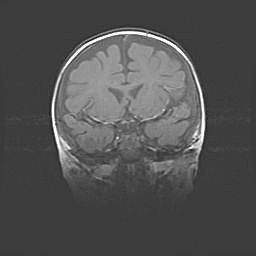

Сообщающаяся гидроцефалия. Кистозная энцефаломаляция головного мозга.

Возраст: 3 месяца 4 дня

Вес: 3100 г

Пол: женский

Окружность головы: 34 см

Срок гестации: 31 неделя

Кистозная энцефаломаляция головного мозга - одна из форм поражения головного мозга в детском возрасте. Характеризуется возникновением множественных и распространённых кист в коре, белом веществе и подкорковых образованиях головного мозга у плодов, новорождённых и детей раннего возраста. Развитие кистозной энцефаломаляции связано с внутриутробной асфиксией и гипотонией, родовой травмой, тромбозом синусов, пороками развития сосудов, инфекциями, сепсисом и другими причинами. Наиболее значимые инфекционные агенты: вирусы простого герпеса, цитомегалии, краснухи, токсоплазмы, энтеробактерии, золотистый стафилококк и другие.